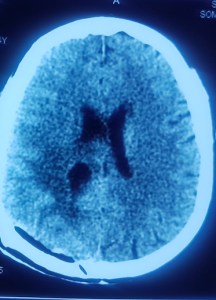

Pacienta noastră, doamna Toma, prezenta la internare tulburări de echilibru, de mers și de vedere, precum și deficit motor hemicorp drept și nu urmase decât un tratament operator pentru melanomul malign cutanat, fără un tratament oncologic adjuvant. Însă, după un examen RMN 3T cerebral (cu ajutorul unui aparat de ultimă generație RMN, singurul din țară, disponibil pentru toți pacienții în cadrul spitalului Sanador), și un examen CT la craniu (cu substanță de contrast), s-a stabilit diagnosticul de metastază cerebrală occipital stânga profundă, în vecinătatea unor structuri importante ale creierului (sistem ventricular, corpul calos etc.)

S-a reușit astfel îndepărtarea în totalitate a tumorii cerebrale, folosind cel mai modern microscop operator ”ZEISS KINEVO 900” (de asemenea, prezent în blocul operator al spitalului Sanador).

Tumoarea cerebrală a fost eliminată complet cu ajutorul intervenției chirurgicale

Doamna Toma și-a revenit imediat după ce efectul anesteziei a trecut. Aceasta a reușit să recupereze tulburările cu care se prezentase inițial la spital, după o zi petrecută la reanimare și alte patru zile de internare în cadrul secției de neuorchirugie. Examenele CT realizate după operație au indicat faptul că tumorăa a fost extirpată în totalitate, ceea ce confirmă faptul că operația a fost un real succes!